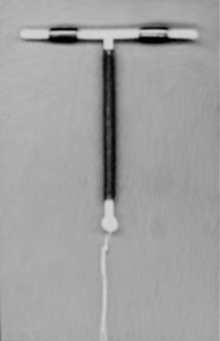

An intrauterine device (IUD or coil)[1] is a small contraceptive device, often 'T'-shaped, often containing either copper or levonorgestrel, which is inserted into the uterus. They are one form of long-acting reversible contraception which are the most effective types of reversible birth control.[2] Failure rates with the copper IUD is about 0.8% while the levonorgestrel IUD has a failure rate of 0.2% in the first year of use.[3] Among types of birth control they, along with birth control implants, result in the greatest satisfaction among users.[4] In 2007, IUDs were the most widely used form of reversible contraception, with more than 180 million users worldwide.[5]

Most copper IUDs have a plastic T-shaped frame that is wound around with pure electrolytic copper wire and/or has copper collars (sleeves). The arms of the frame hold the IUD in place near the top of the uterus. The Paragard TCu 380a measures 32 mm (1.26") horizontally (top of the T), and 36 mm (1.42") vertically (leg of the T).